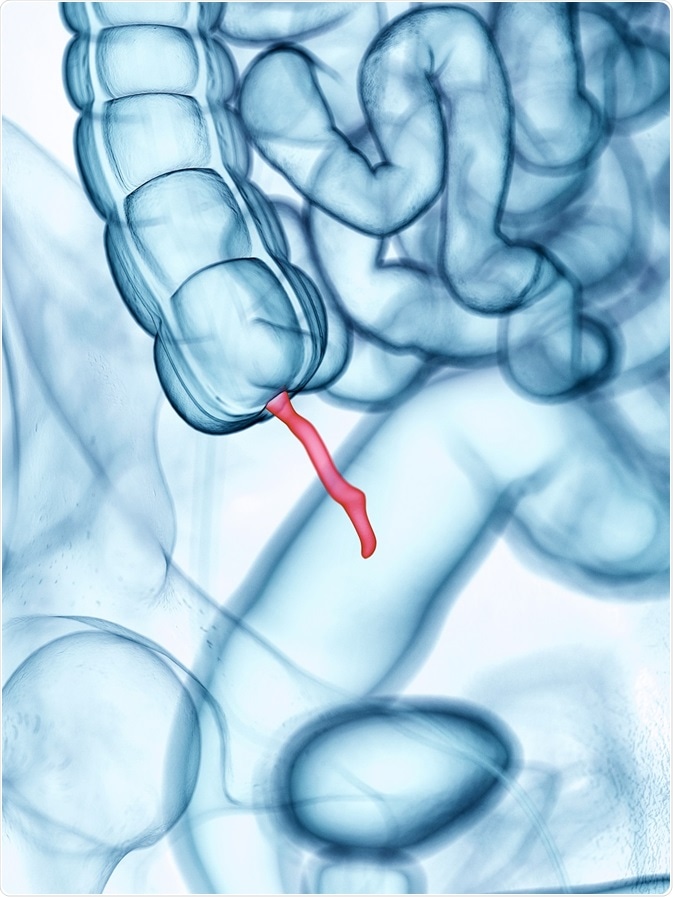

Pseudomyxoma peritonei (PMP) typically starts as a slow-growing tumor in the appendix, and it is hence classified as a low-grade mucinous appendiceal neoplasm (LAMN). In rare instances, it may develop in other organs, such as the ovary, bowel, or bladder.

Credit: Sebastian Kaulitzki/ Shutterstock.com